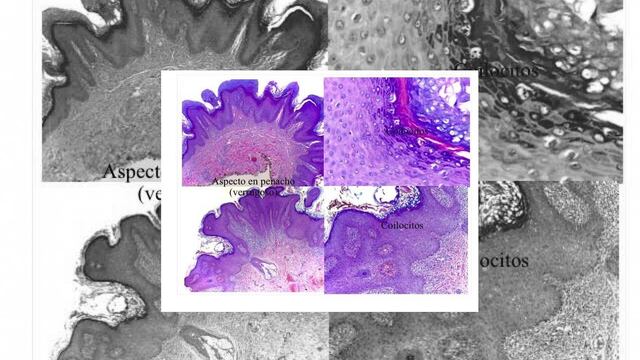

¿A quién acudir si se encuentra una lesión que parece un penacho (aspecto verrugoso)? ¿A quién preguntarle? La respuesta es muy sencilla, a los especialistas mejor informados, esto son dermatólogos, ginecólogos y urólogos.

¿Existe el potencial de contagio? Siempre que existan células infectadas existe este potencial. Es decir, si observamos lesiones con apariencia de ?penacho? o si en el examen de las células (en cérvix o uretra) teñidos con Papanicolaou existen los famosos coilocitos. Prueba que debe realizarse desde que se tienen relaciones sexuales, no importando si le conocemos o desconocemos. Ya saben, ¡caras vemos, papilomas desconocemos!